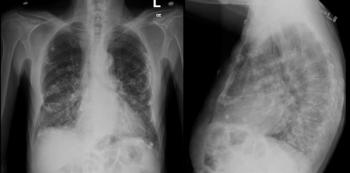

44-year-old female presents with “cord-like,” palpable lump on left breast.